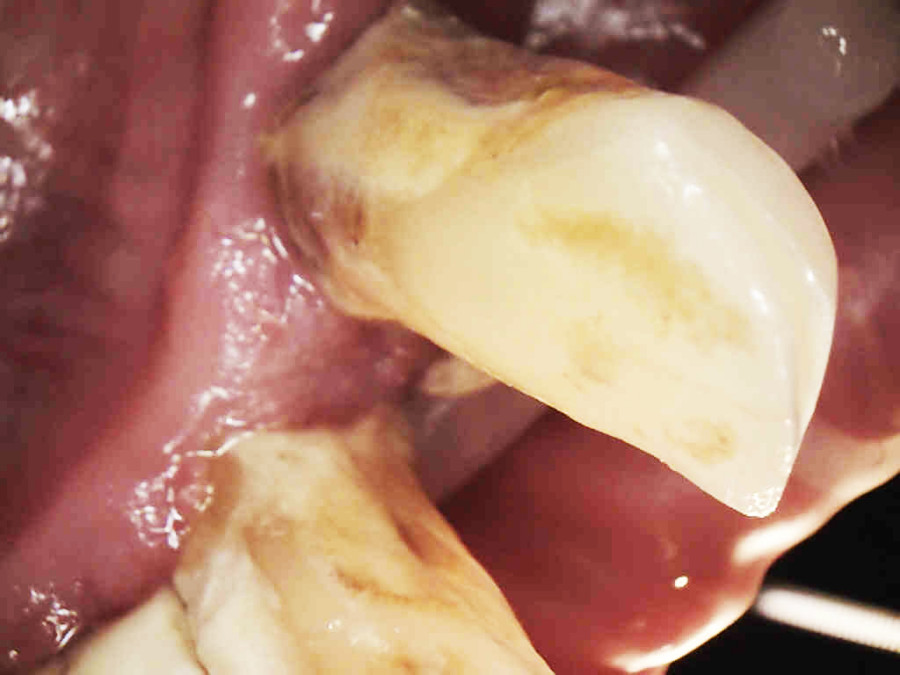

Pacjentka lat 65, zgłosiła się do stomatologa na konsultację, ponieważ niepokoiła ją ruchomości zębów. W pierwszej kolejności została skierowana na wizyt higienizacyjną. Bezzębie w łuku górnym zaopatrzone było całkowitą akrylową protezą, w łuku dolnym pacjentka nie użytkowała żadnego uzupełnienia. Pacjentka niepaląca.

Postępowanie rozdzielono na dwie wizyty. Badaniem klinicznym, oceniając wskaźniki periodontologiczne, uzyskano wartości API 100%, PBI 100% świadczące o konieczności poprawy higieny i procesie zapalnym dziąseł, duże złogi kamienia nad i poddziąsłowego, bardzo obfity biofilm, pogłębione wszystkie kieszonki dziąsłowe, ciężkie zapalenie dziąseł, ruchomości zębów dolnych III stopnia, duży zanik kości. Badanie kliniczne błony śluzowej jamy ustnej nie wykazało zmian patologicznych.